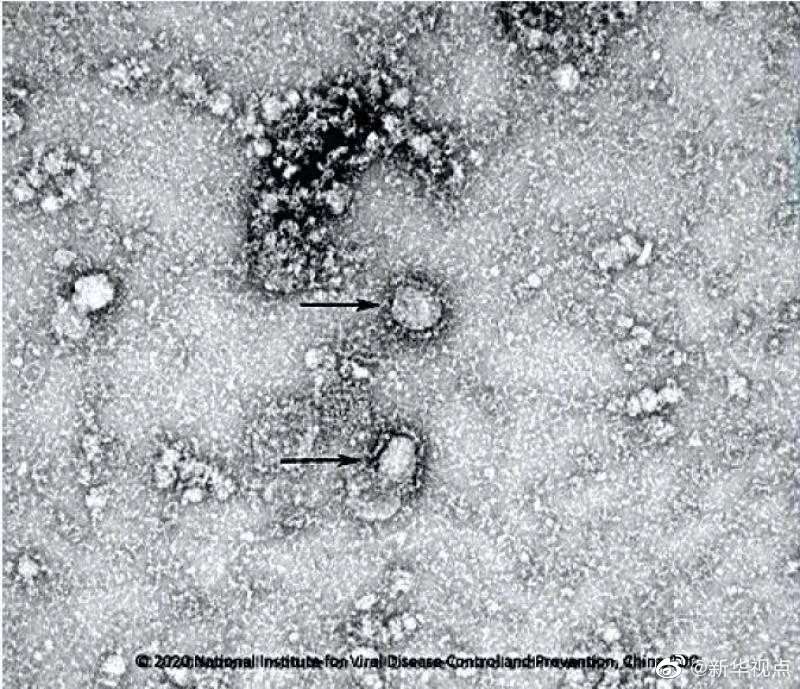

1. 好消息!中國疾控中心成功分離我國首株新型冠狀病毒毒種,它長這樣!

國家病原微生物資源庫于2020年1月24日發(fā)布了由中國疾病預防控制中心病毒病預防控制所成功分離的我國第一株病毒毒種信息及其電鏡照片、新型冠狀病毒核酸檢測引物和探針序列等國內(nèi)首次發(fā)布的重要權威信息,并提供共享服務。看病毒“真容”↓↓↓(記者田曉航、王秉陽)